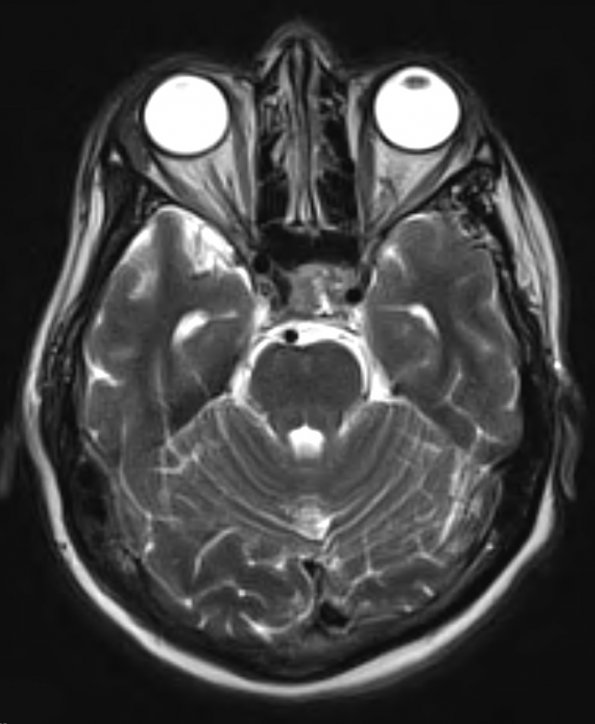

8A4 PA & GGL diffn (Case 8) T2 1 - Copy - Copy

The T2-weighted image shows minimal hyperintensity.